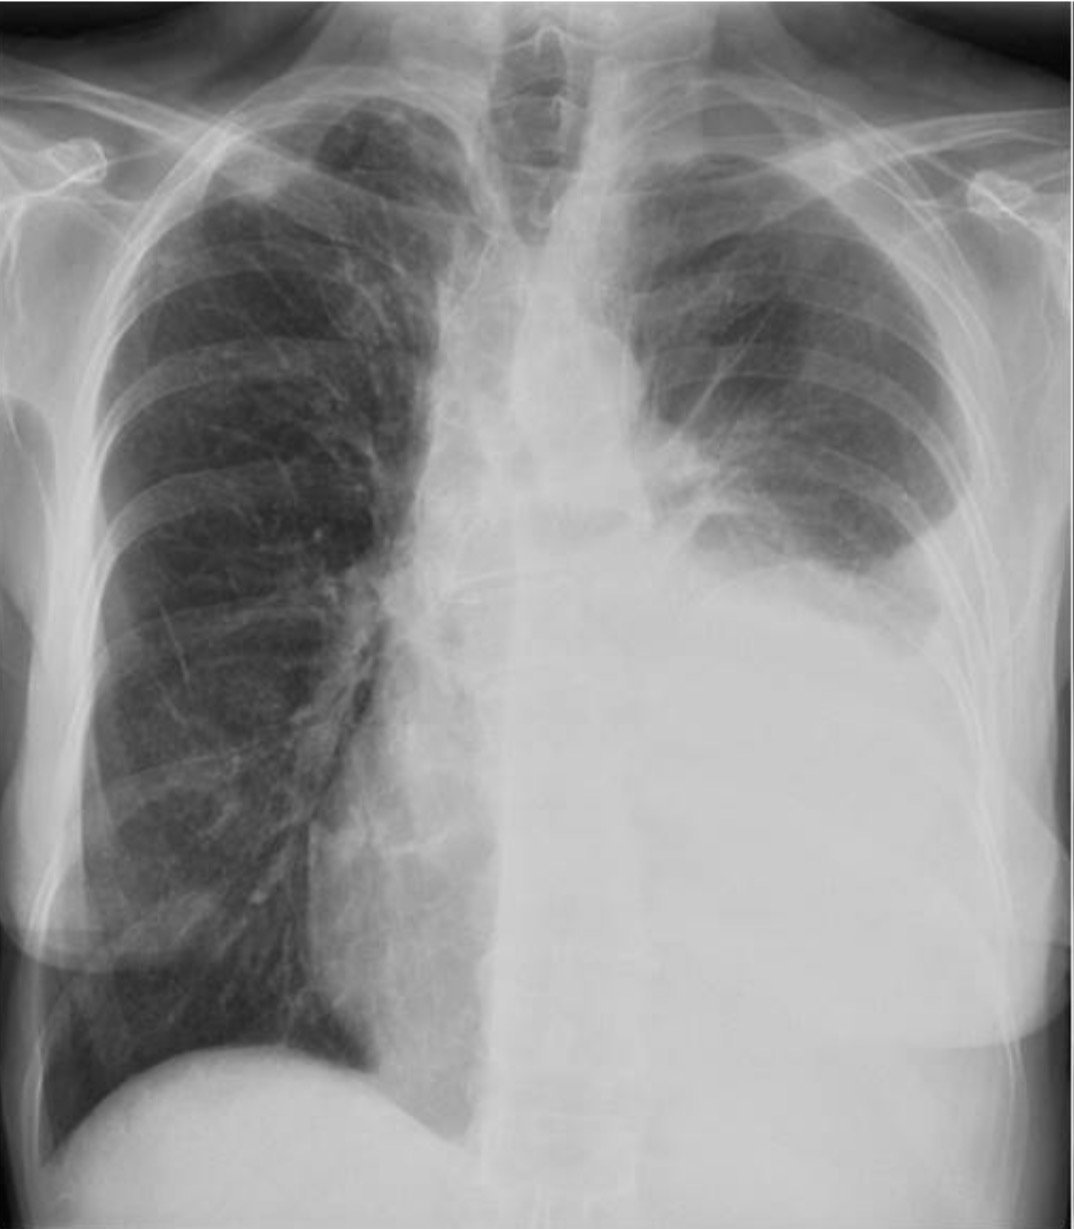

Rx PA tórax

HALLAZGOS RADIOLÓGICOS

Opacidad homogénea bien delimitada en el hemitórax izquierdo sin desplazamiento mediastínico hacia la izquierda.

Opacidad homogénea mal delimitada en el hemitórax izquierdo sin desplazamiento mediastínico hacia la izquierda.

Opacidad homogénea bien delimitada en el hemitórax izquierdo con desplazamiento mediastínico hacia la izquierda.

Opacidad homogénea mal delimitada en el hemitórax izquierdo con desplazamiento mediastínico hacia la izquierda.